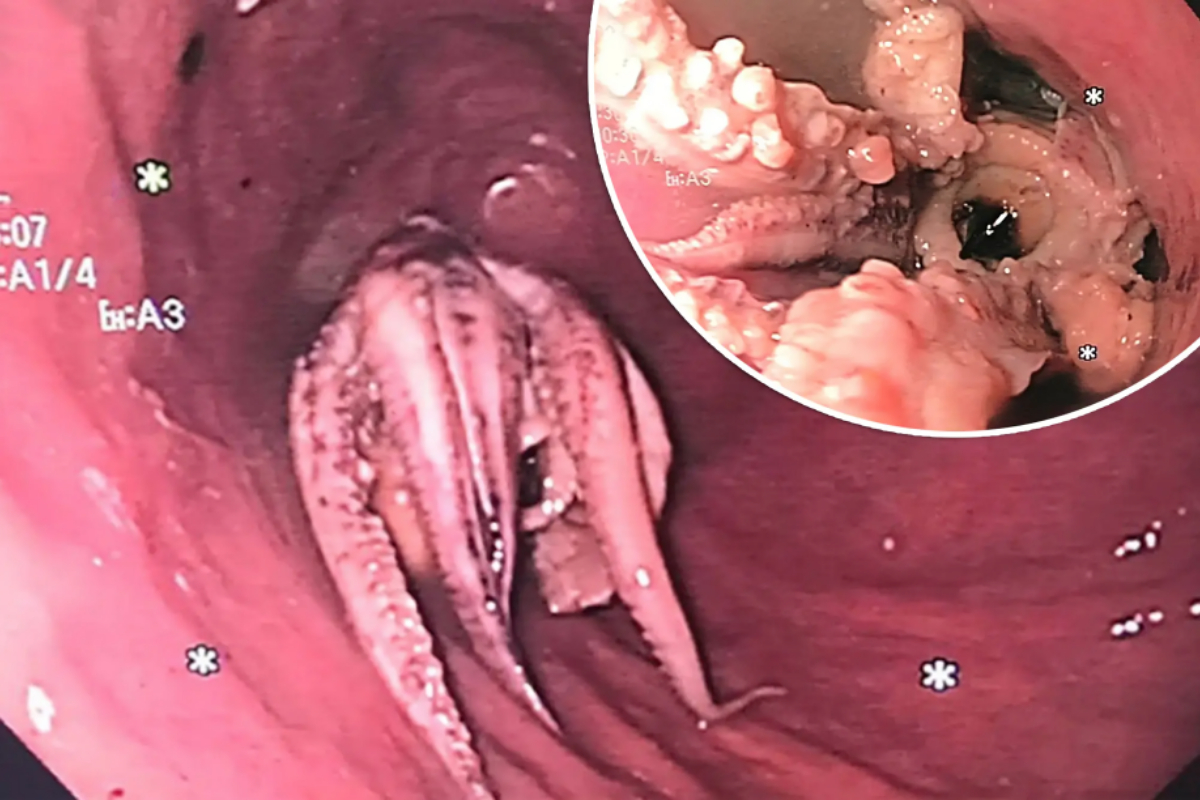

Man’s Esophagus Contains Whole Octopus, Baffling Doctors

Doctors in Singapore were astonished when they found a whole octopus stuck in a man’s esophagus during a gastrointestinal examination. The unnamed Singaporean man experienced vomiting after consuming a meal that included raw octopus. Concerned by his difficulty swallowing, he rushed to the emergency room at Tan Tock Seng Hospital. A CT scan revealed a dense mass in the man’s